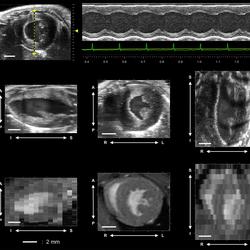

The power of 4D technology advances care for heart patients

A tool that has been around for decades shows new promise in helping people with heart disease. A new study published in the Annals of Internal Medicine finds that adding ultrasound imaging during the doctor’s assessment of cardiac function could help improve diagnoses and treatments.